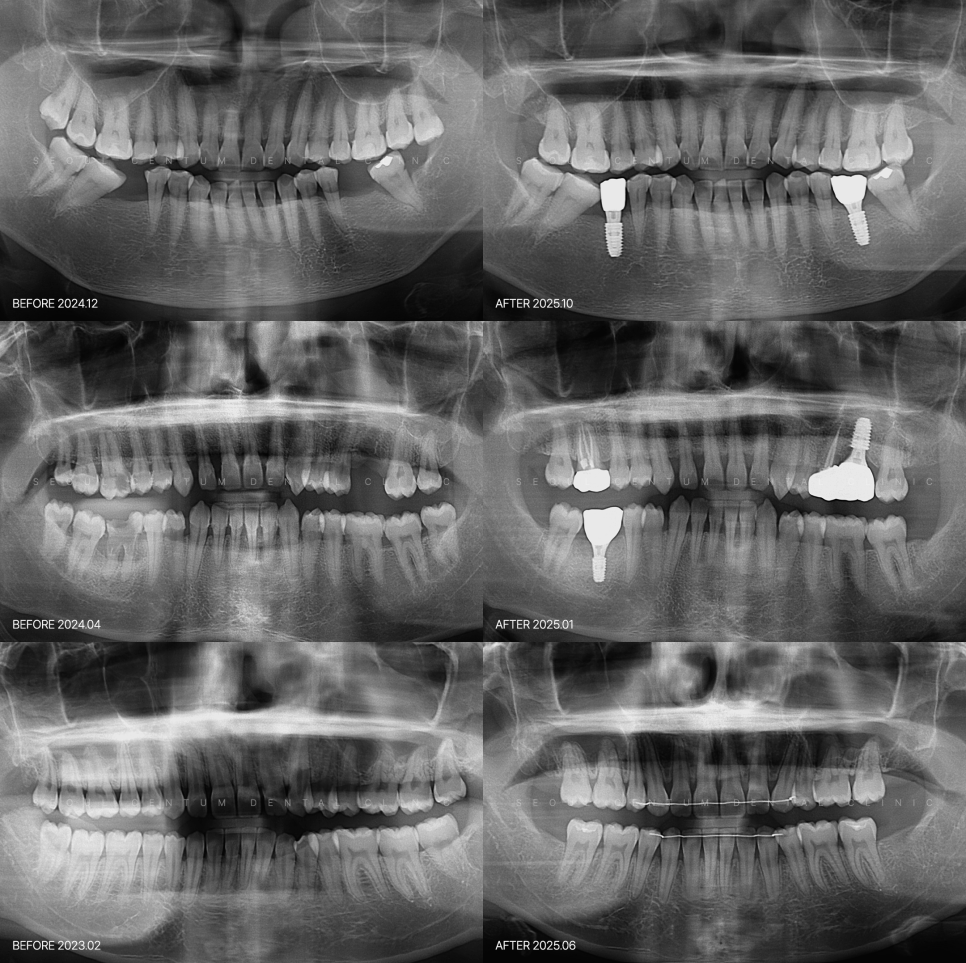

사전 진단을 기반으로 진행해야 하기 때문에

구강 검진과 더불어

파노라마 영상이나 CT 촬영을 통해

사랑니의 깊이, 신경과의 거리,

치근 형태 등을 면밀히 분석합니다.